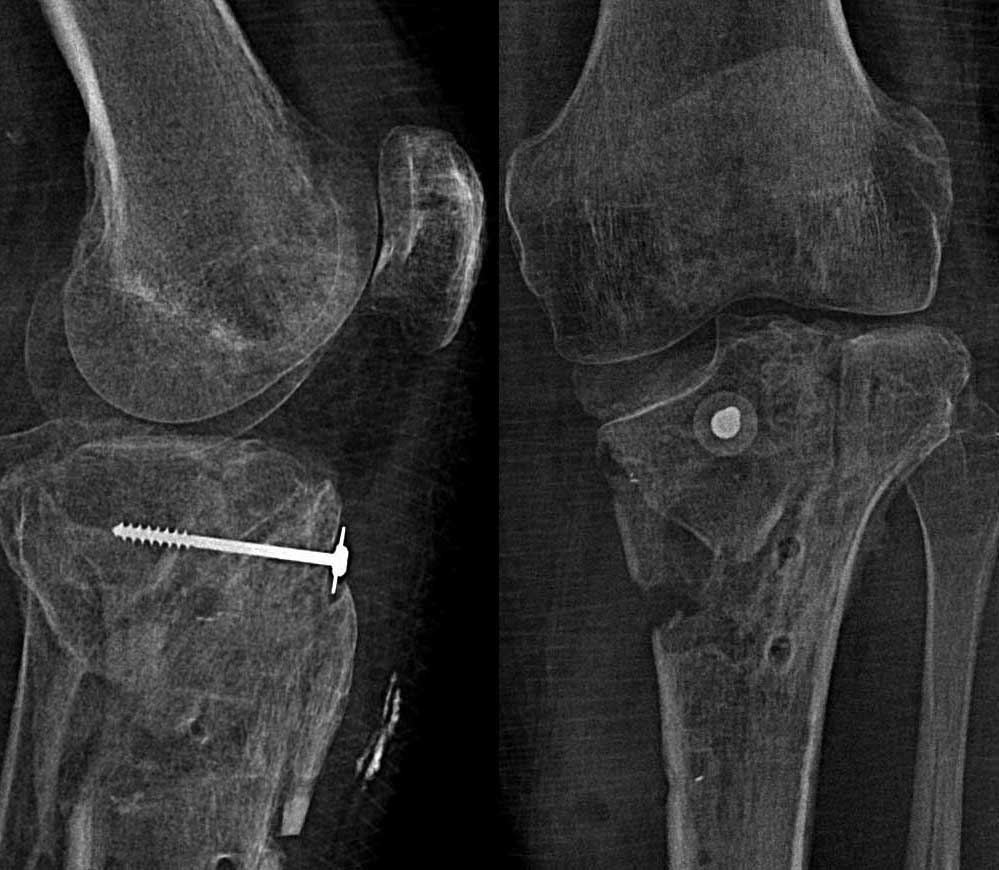

[Ortho] Оскольчатый перелом внутреннего мыщелка + комбинированная нестабильность

После удаления фиктасторов